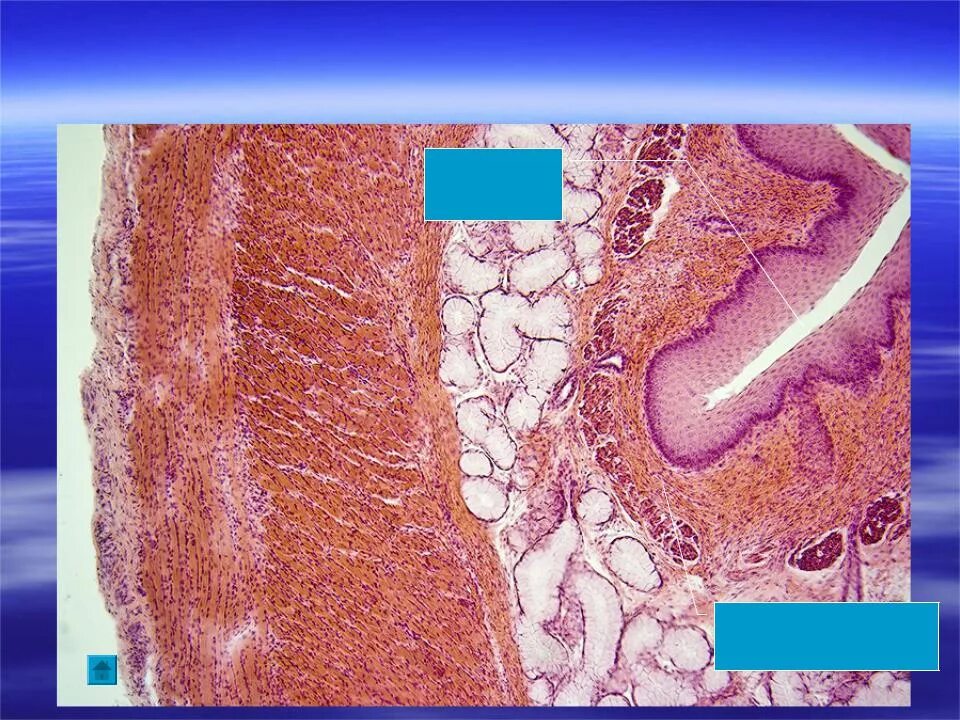

Гистологические препараты соединительная ткань